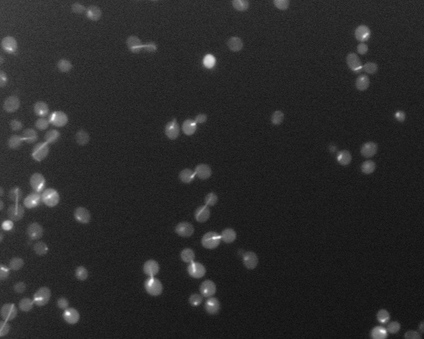

Identification of blood cells in microscope images

- Task: Automatically count and identify all the cells present in a given a microscope image. Note that a method to identify pixels that may lay on the edge of cell (edgels) based on frequency analysis was provided as start code.

- Abstract: To form initial cell location proposals, local groups of edgels that may lie on the boundary of the same cell are detected by a connected components method over the set of all edgels. For each component, two random edgels are selected, assumed to be on the boundary of the cell, and the intersection of their normals is computed as a proposal for the center of the circle and accompanying radius. If the normals do not intersect, or intersect at an improbable distance, the proposal is rejected and new edgels selected. A scoring function evaluates circle proposals for the cell based on how many edgels lie on the proposed circles and edge compared to how many lay within it, generally favoring smaller circles. This allows edgels that originate from a dividing cell, or overlapping cells, to be accurately divided into multiple circles. The highest scoring circle is choosen over several RANSAC trials and the edgels on the boundary of the circle are removed from the overall set in the graph, continuing until no edgels or valid circle proposals remain.